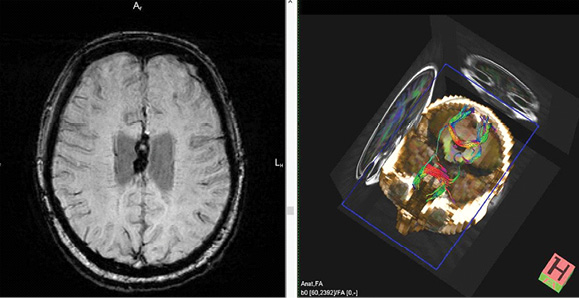

Рисунок 4. Последствия ЧМТ. Слева – ДТ МРТ. Разрыв проекционных трактов в области кистозно-глиозных изменений. Справа – режим T2-ВИ. Аинтенсивный сигнал по периферии кистозно-глиозных изменений (отложения гемосидерина).

Figure 4. Consequences of TBI. Left – DT MRI. Rupture of the projection tracts in the area of cystic-gliotic changes. Right – T2-WI mode. Aintensive signal on the periphery of the cystic-gliotic changes (depositions of hemosiderin).

ДТ МРТ расценивает степень целостности проводящих путей, различие в миелинизации волокон, их диаметр. В основном определяют ход самых больших комиссуральных и проекционных трактов ГМ: мозолистого тела, кортикоспинальных трактов и волокон, проходящих через внутреннюю капсулу (рисунки 3

и 4) [2, 5, 9].

У лиц, перенесших дислокационный синдром со сдавлением ножки ГМ, в последующем формируется дегенерация волокон одного из кортикоспинальных трактов, что сопровождается развитием гемиплегии. ДТ МРТ у людей с ЧМТ используют для оценки динамики течения ДАП и в диагностике постдислокационных изменений [2]. При ДАП из-за дегенерации комиссуральных и восходящих нервных волокон через 3–4 месяца после ЧМТ фиксируется феномен «облысения» мозолистого тела, что представляется неблагоприятным прогностическим знаком восстановления сознания и психической деятельности [9, 24].